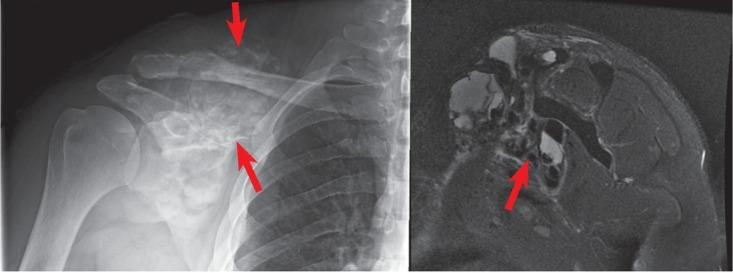

异位骨化:影像学与病理学综述

Heterotopic ossification: radiological and pathological review.

Background Heterotopic Ossification (HO) is a common condition referring to ectopic bone formation in soft tissues. It has two major etiologies, acquired (more common) and genetic. The acquired form is closely related to tissue trauma. The exact pathogenesis of this disease remains unclear; however, there is ongoing research in prophylactic and therapeutic treatments that is promising. Conclusions Due to HO potential to cause disability, it is so important to differentiate it from other causes in order to establish the best possible management.

摘要

背景 异位骨化(HO)是一种常见病症,指的是软组织中异位骨的形成。它有两种主要病因,后天性(更常见)和遗传性。后天性形式与组织创伤密切相关。该疾病的确切发病机制仍不清楚;然而,目前在预防性和治疗性治疗方面的研究很有前景。结论 由于HO有导致残疾的可能性,为了制定最佳治疗方案,将其与其他病因区分开来非常重要。